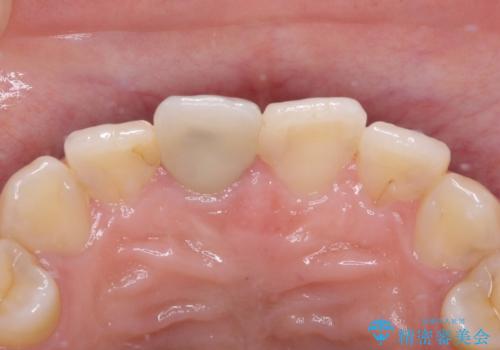

- 数年前に他院で治療した右上の前歯の色が不自然なことを主訴として来院された患者様です。

隣在歯と色、形ともに合っていません。

また、被せものと土台の境目が歯肉よりも上に見えていて、段差になっています。

そのため審美性、清掃性どちらの観点からもあまりよくない状態です。

不適合な被せものを除去し、土台の歯の形を修正し、精度の高いシリコーンによる型どりをしました。